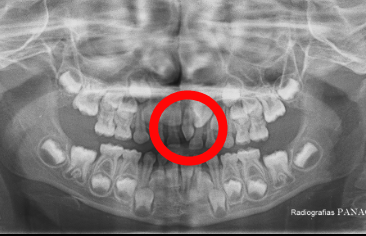

Es paciente femenina de 6 años de edad con hallazgo clínico y radiográfico de mesiodents. Además presencia de diastema interincisal lo que ha ocasionado timidez en la interrelacion de la portadora al sonreir (sonrisa labial, sin mostrar dientes) al interrogatorio la representante refiere burlas en la escuela por su condición.

Despues del examen realizado se procedio a planificar intervención quirurgica simple para la extración del mesiodent. Acto operatorio sin complicación postoperatorio mediato a los 3 dias satisfactorio; se observa aumento de autoestima y confianza al sonreir.